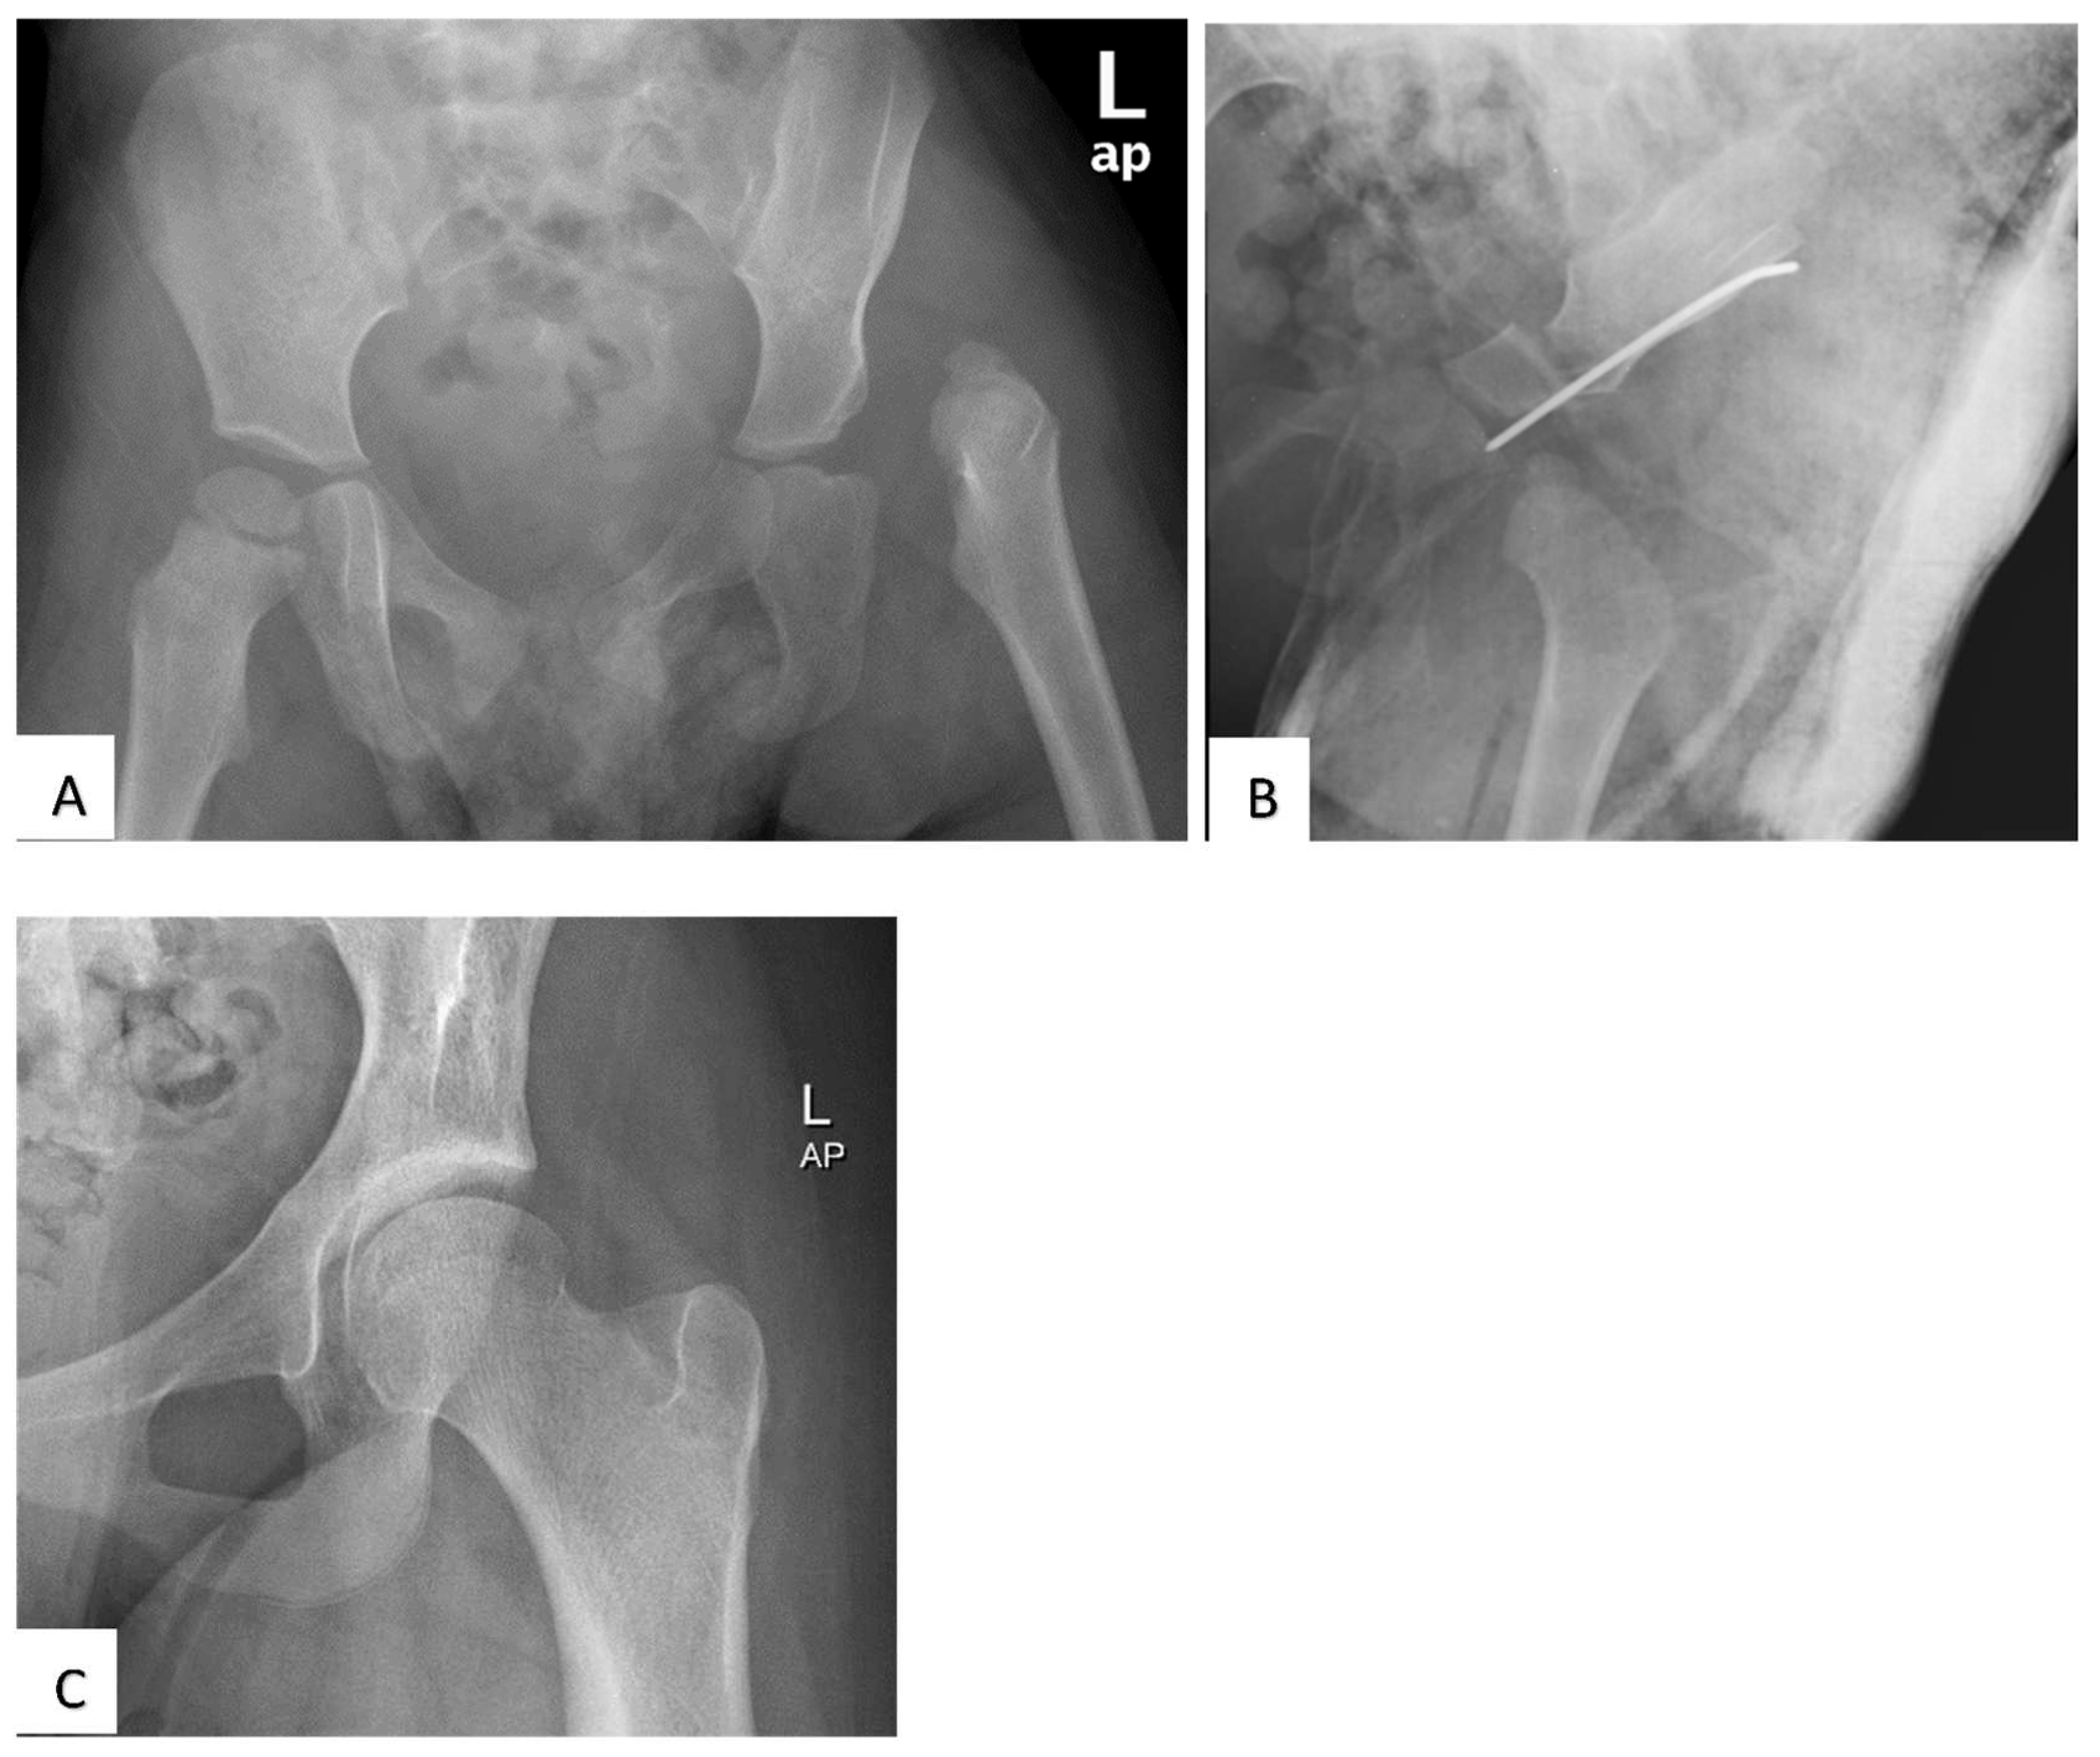

Outcome of Open Reduction Alone or with Concomitant Bony Procedures for Developmental Dysplasia of the Hip (DDH)

2. Materials and Methods

3. Results